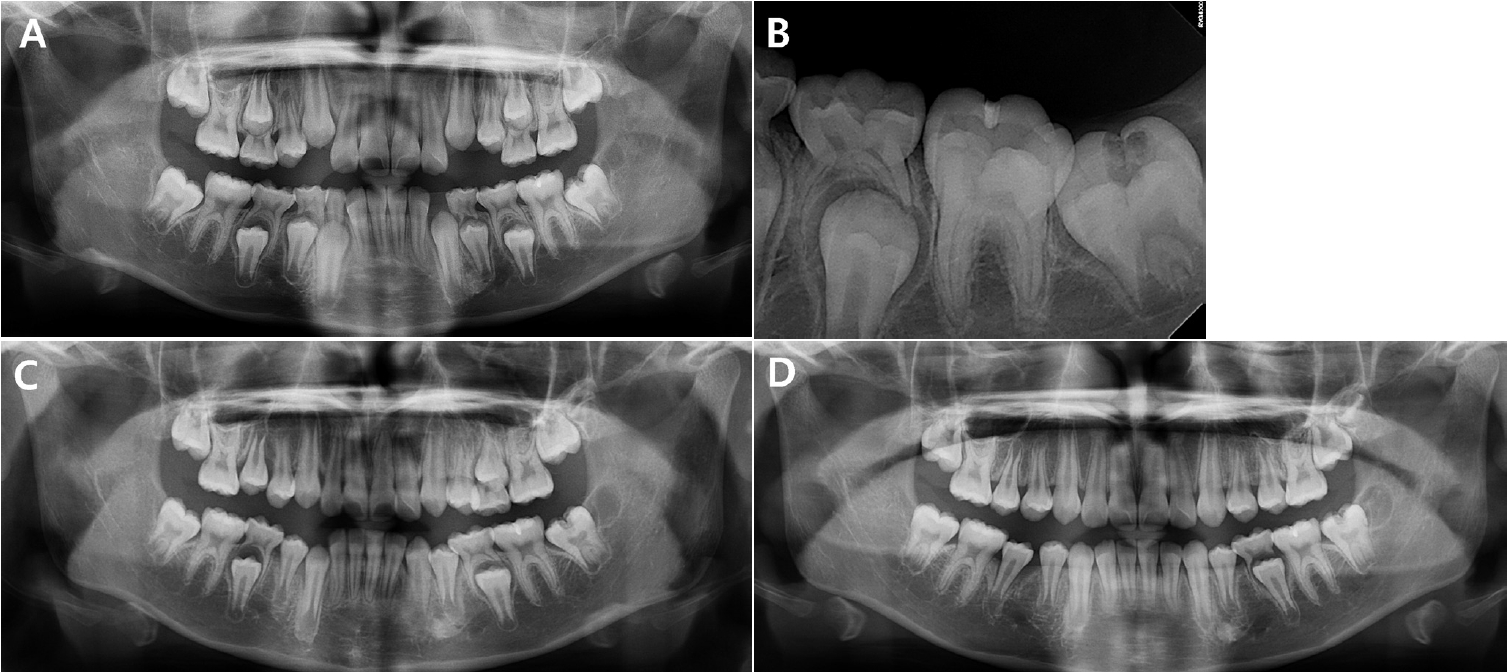

맹출 전 치관 내 흡수 치아의 수복 치료: 증례 보고

Su-Hyun Park, Myeong-Kwan Jih, Nan-Young Lee

2025;63(12):399-405. Published online December 31, 2025